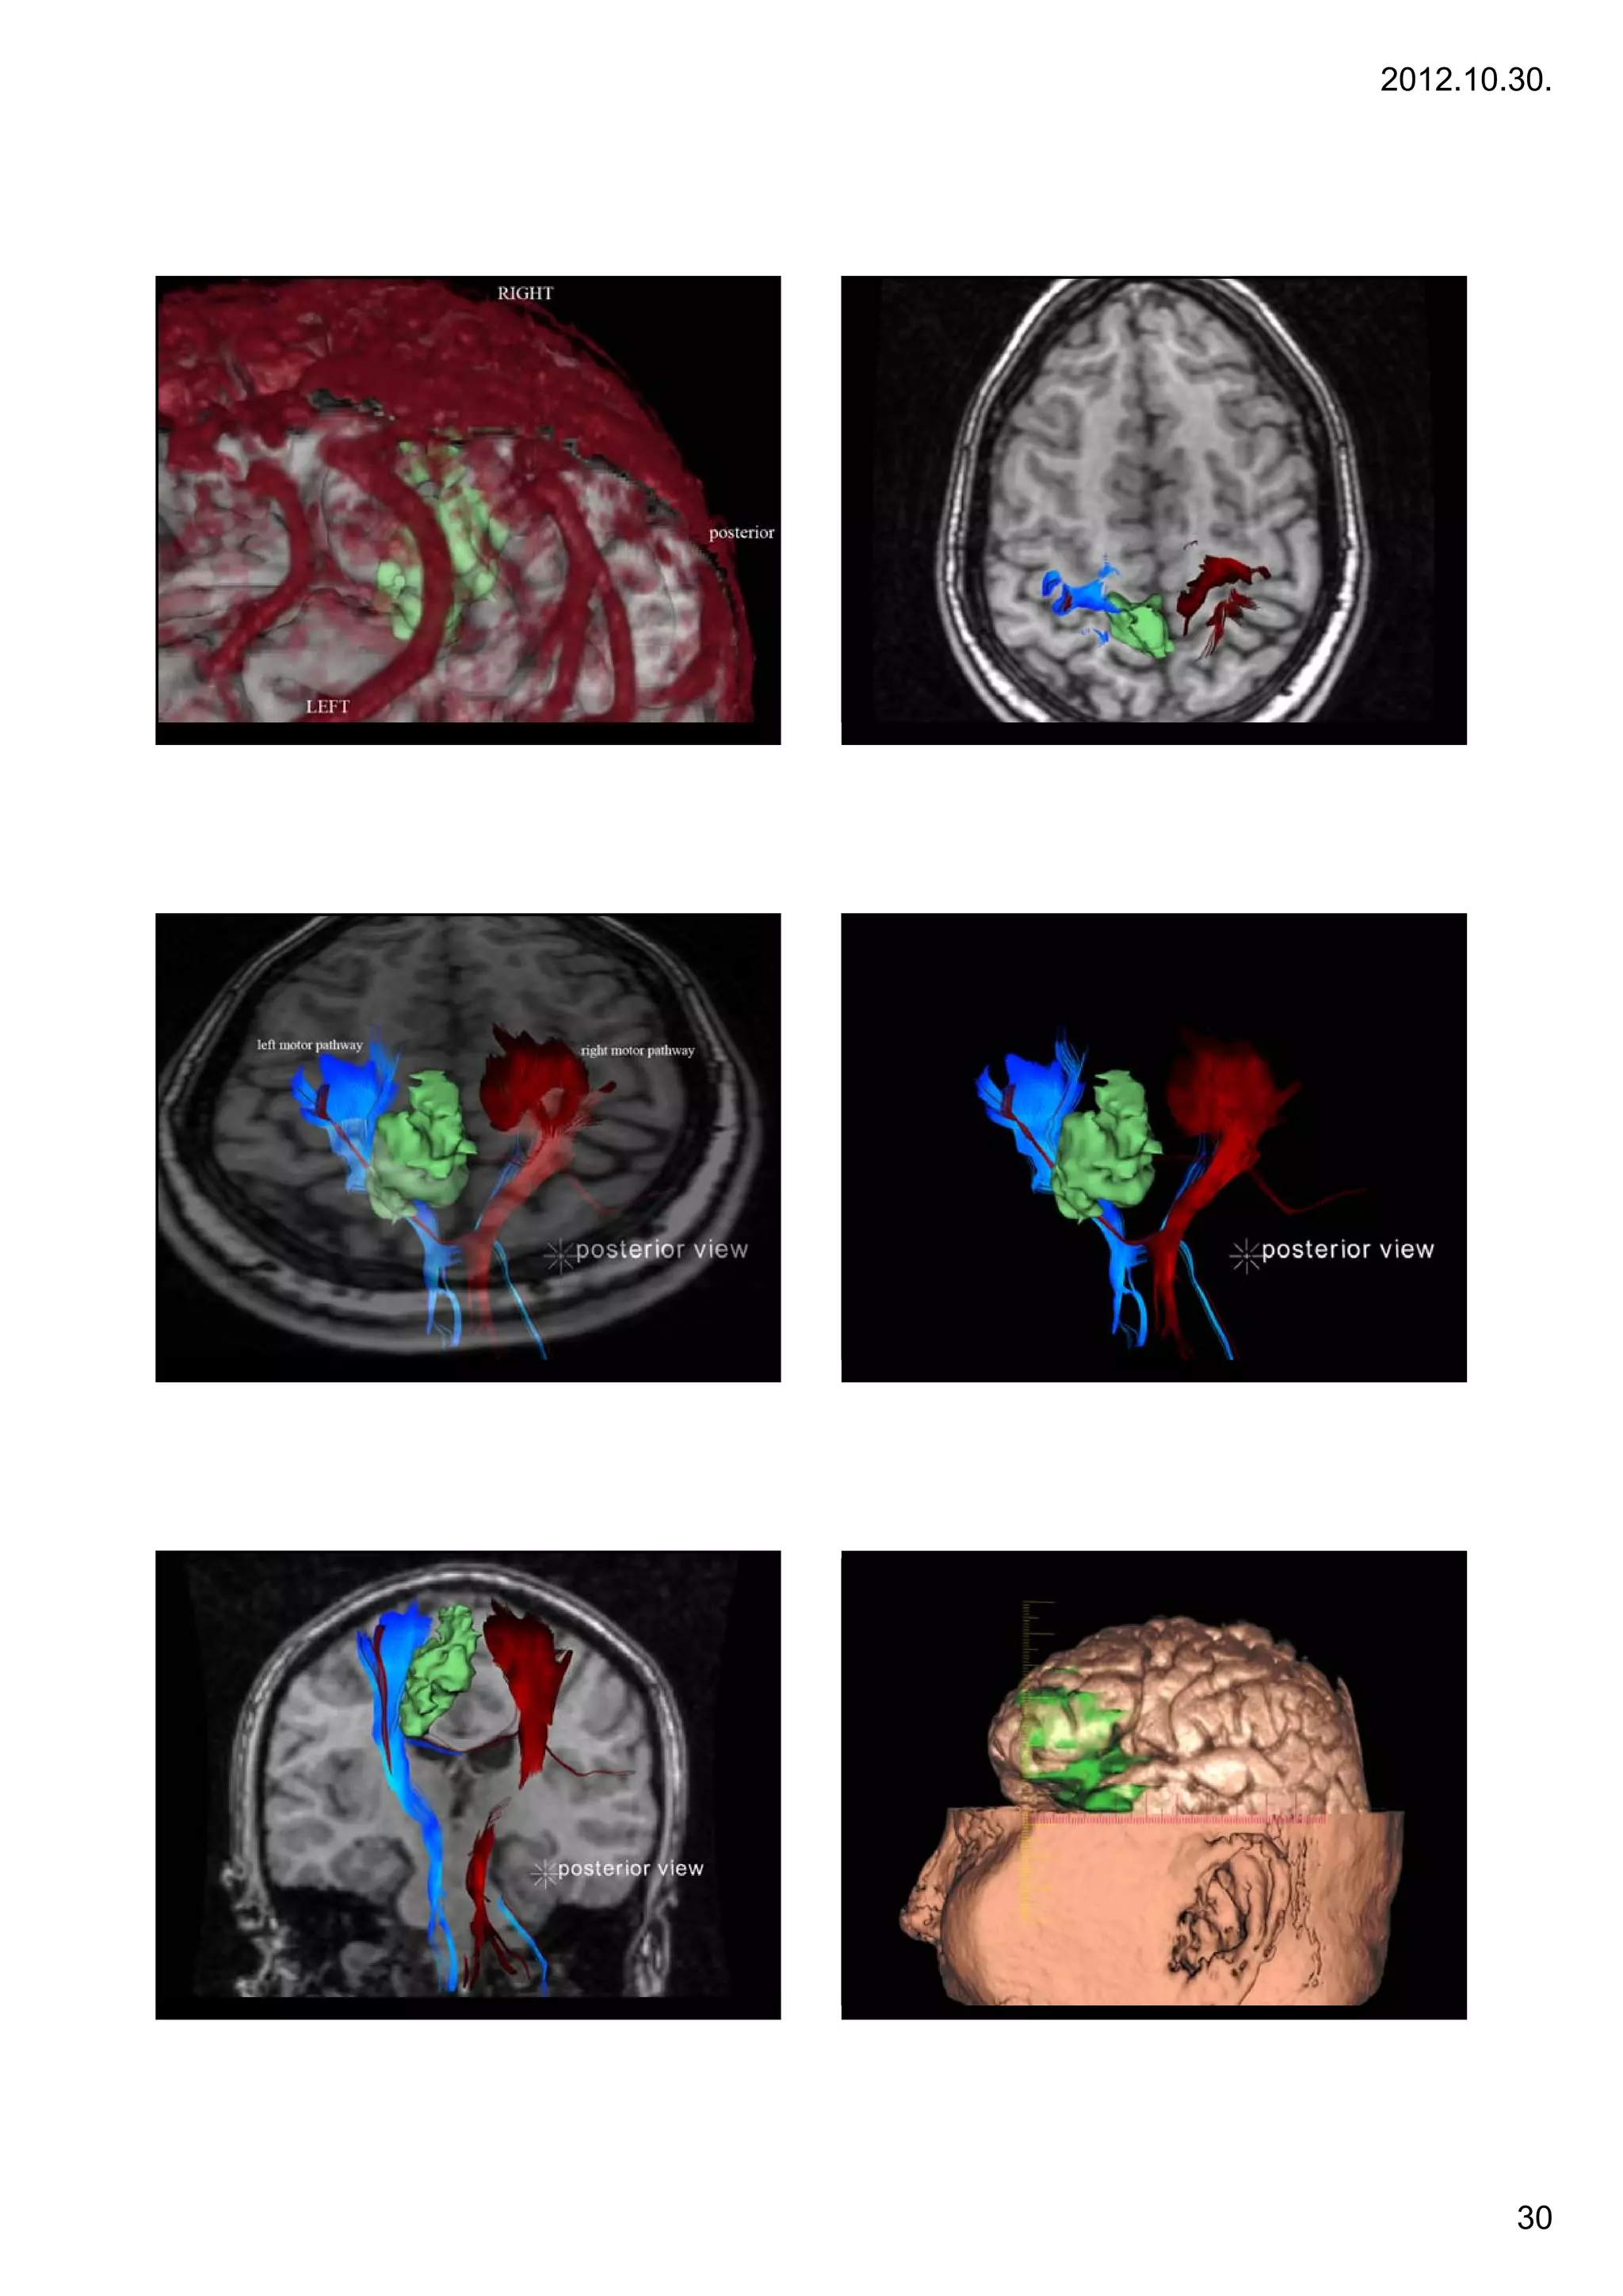

Case 7. – large GBM

Treatment: d b lki

T           debulking

32